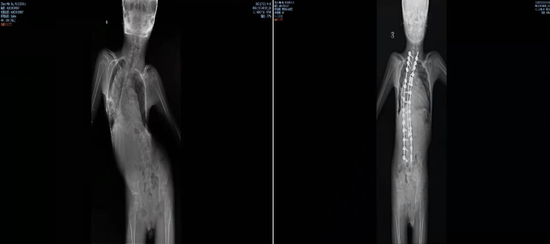

图/手术前后对比图  来源/ 受访者供图

脊柱的扭曲,增加了寻找药物的鞘内注射点,让药物顺利进入到椎管内的难度。儿科接诊后反复与各科室沟通,最终决定让小乐先接受脊柱畸形矫形手术治疗。

2021年9月,李淳德在完成脊柱畸形矫正手术的同时,还要切除部分腰椎椎板,为后面注射药物预留出骨性通道。虽然手术顺利,但术后小乐的腰部无法弯曲,已经没有同正常人一样的解剖标志,预留的通道也很难找到。麻醉科副主任胡晓通过超声引导反复摸索,寻找到预留的骨性通道,最终穿刺成功,完成国内首次SMA脊柱畸形矫形术联合诺西那生鞘内注射。